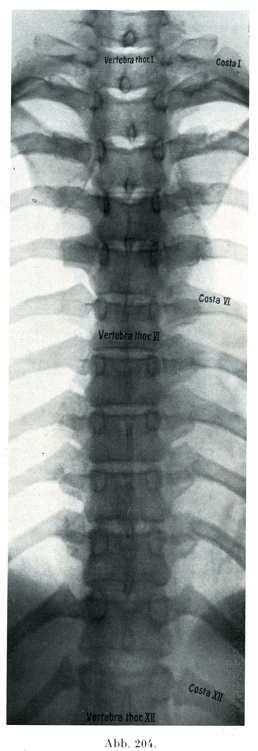

[図204]20才の男子の胸部脊柱レントゲン写真 腹背照射(6/11).